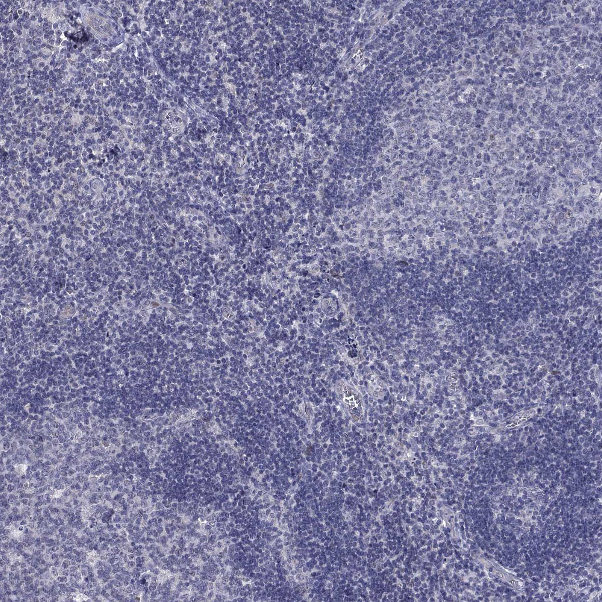

Immunohistochemistry analysis in human small intestine and liver tissues using HPA040591 antibody. Corresponding HTR4 RNA-seq data are presented for the same tissues.